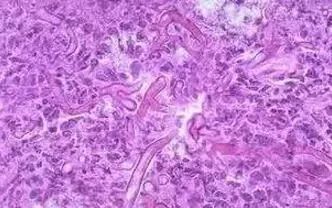

1、真菌性阴道炎

临床表现:豆渣样白带,阴道分泌物检查时可以见到菌丝和孢子,细菌培养可以培养 出白色念珠菌落,好发于月经前。